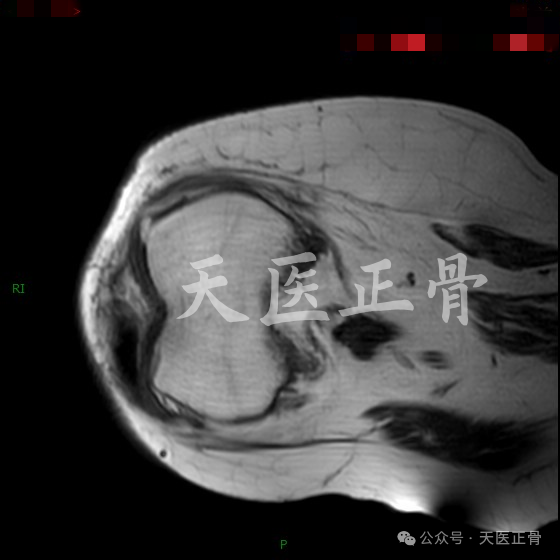

膝关节矢状位MR图像

膝关节水平位MR图像

显示髌骨在滑车沟内位置良好

根据本例MR的图像可以证实髌骨上极骨赘嵌顿于髁间窝导致髌骨关节内嵌顿的假设,从而引起髌骨关节内水平脱位。